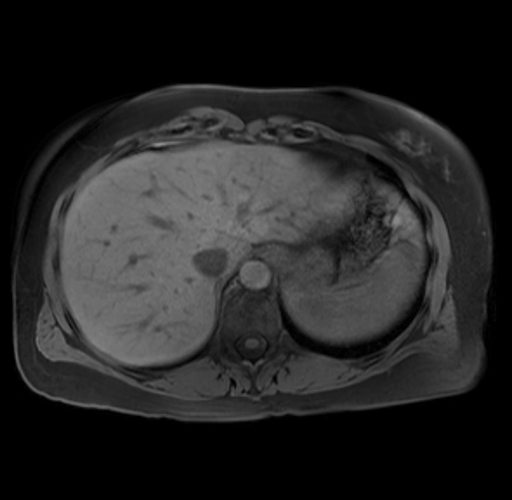

Imaging Analysis

Look through the patient's CT scan to identify any areas of concern for the necessary procedure.

Based on your CT findings, which issue(s) are present and would give reason for "planned slowing down moment(s)" in this case?

Considering a standard distal pancreatectomy procedure, what step(s) of the operation would you do differently in this case?